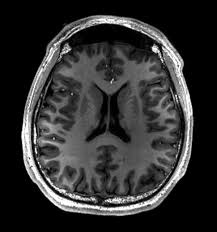

Your brain is always working, processing information, solving problems, and keeping your body running. But just like a factory produces waste as it operates, so does your brain. This is where the glymphatic system comes in, it’s your brain’s built-in cleaning service.

The glymphatic system is a network of fluid-filled channels that remove toxic waste using cerebrospinal fluid (CSF), a clear liquid that surrounds the brain and spinal cord.

Throughout the day, your brain accumulates waste products like beta-amyloid, a sticky protein linked to Alzheimer’s disease. During sleep, the glymphatic system becomes 10 times more active, flushing out these toxins and keeping the brain healthy.

If we never slept, our brains would slowly clog up with waste, leading to memory loss, confusion, and eventually neurodegenerative diseases.